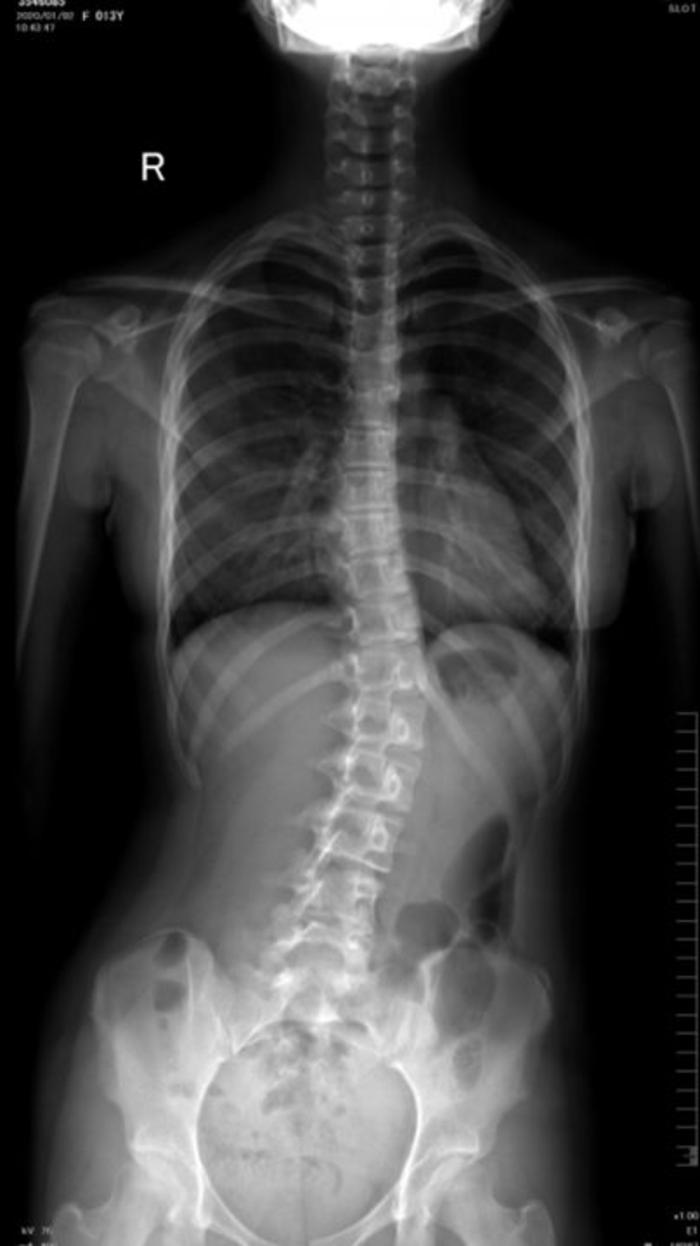

初诊:2020年1月,患者女13岁,例假一年有余,一年前发现脊柱侧弯约17°,未予以及时的重视,经过一年发展,再检查已加重至25度。经医生建议佩戴矫形器,在外地支具室看过部分矫形器后感觉比较笨重,外观相对较差,孩子比较抗拒,经网上了解到3D打印技术,遂至我院3D打印中心门诊就诊。

临床检查:患者risser征3级,体表剃刀背明显,scoliometer测量旋转约15度。

患者穿戴支具后拍片,效果明显。侧弯角度明显降低,且无明显不适感,旋转度和力线均有好转。